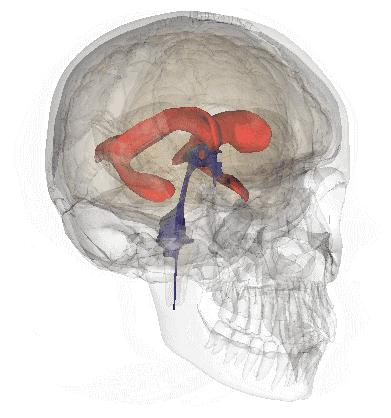

3. 大脑供血动脉 3D 扫描 CT 成像

点击图片可查看大图详情